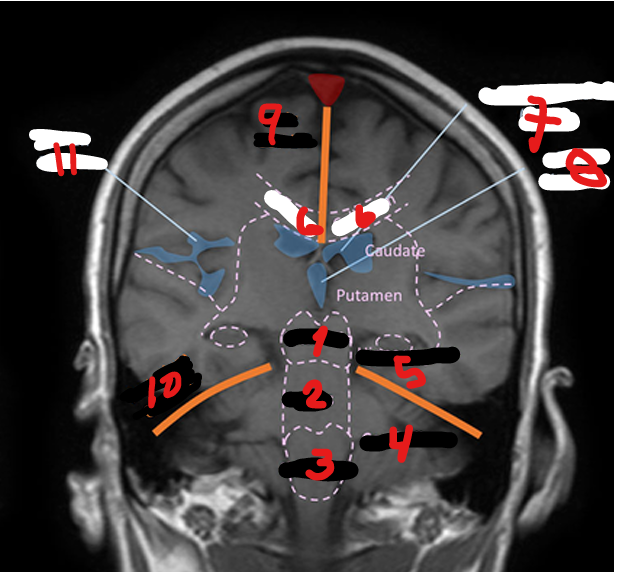

MIDBRAIN

1

<p>1</p>

57

New cards

PONS

2

<p>2</p>

58

MEDULLA

3

<p>3</p>

59

CEREBELLUM

4

<p>4</p>

60

HIPPOCAMPUS

5

<p>5</p>

61

CORPUS CALLOSUM

6

<p>6</p>

62

LATERAL VENTRICLE

7

<p>7</p>

63

THIRD VENTRICLE

8

<p>8</p>

64

FALX CEREBRI

9

<p>9</p>

65

TENTORIUM CEREBELLI

10

<p>10</p>

66

SYLVIAN FISSURE

11

<p>11</p>